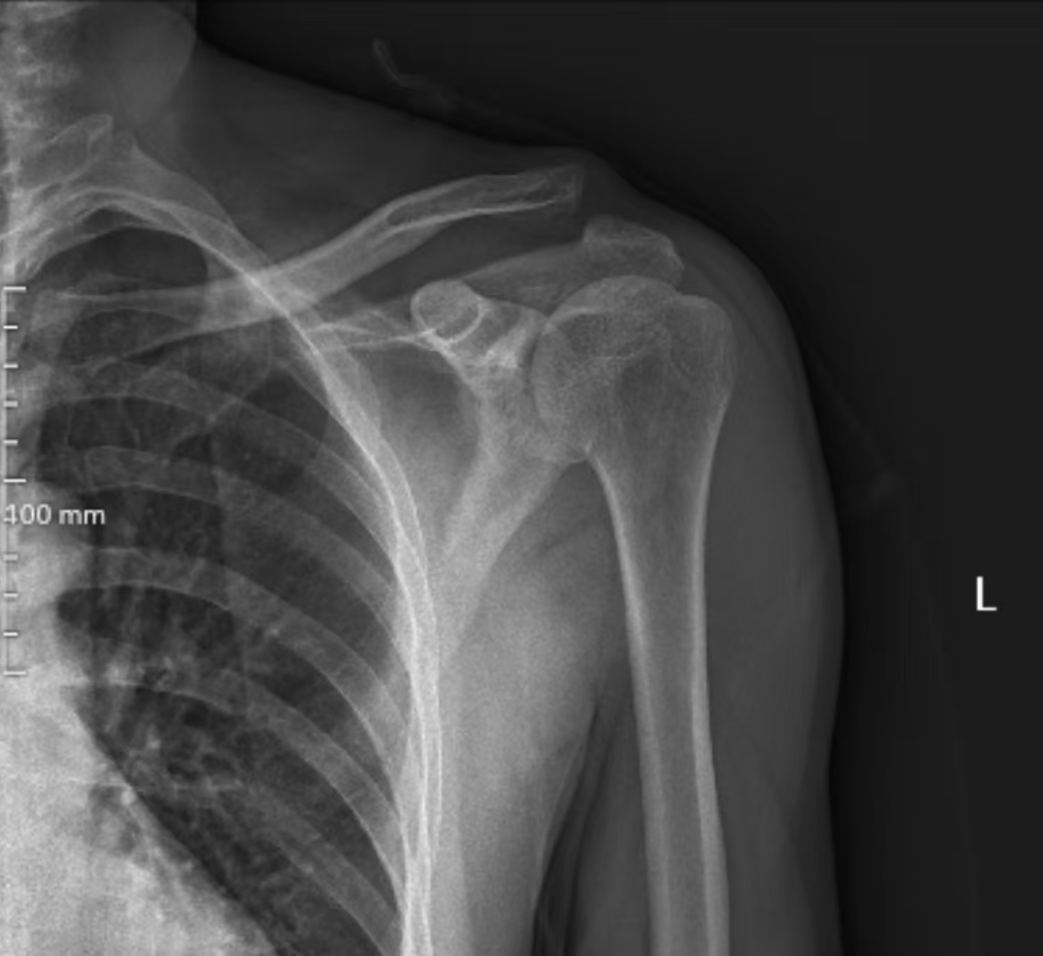

患者刘先生因“摔伤致左肩关节疼痛、活动受限19小时”入院,查体可见左锁骨远端明显突起、压痛,肩关节活动受限。结合影像学检查,确诊为左侧肩锁关节脱位(Rockwood III型),传统保守治疗难以恢复关节稳定性,手术治疗是最佳选择。

手术过程顺利,术中精准复位脱位关节,骨道位置精准且仅有3毫米,完美重建韧带结构。术后X线片显示肩锁关节解剖复位满意,内固定位置良好,患者疼痛明显缓解,肩关节功能逐步恢复。